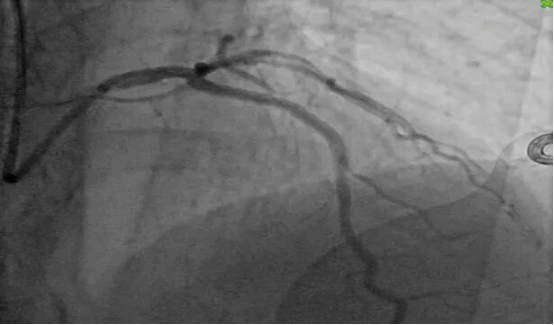

2. 支架植入:先后植入2枚药物洗脱支架;

(术后多角度造影图像)